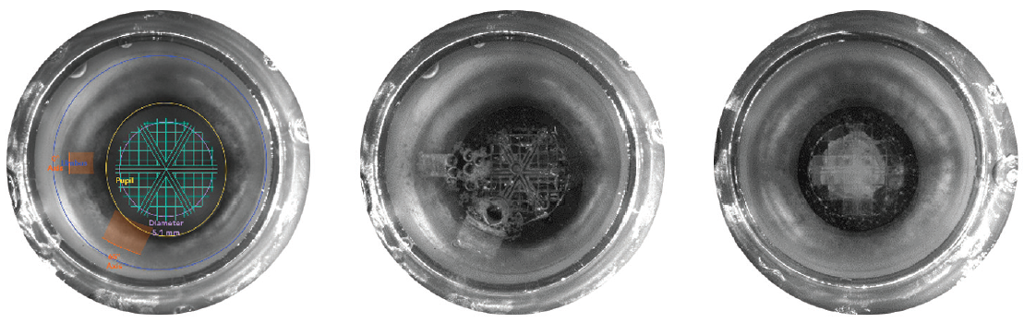

The evaluation of the results of femto-assisted cataract surgery after preliminary YAG laser exposure showed that the fragmentation of lens nuclei with third- and fourth-degree densities using 3.5 and 8.17 J femtolaser energy achieved complete separation of the lens nucleus (Fig. 4). The use of the selected FSL parameters allowed the fragmentation of the lens nucleus along its entire thickness, excluding excessive formation of cavitation bubbles, which technically caused no complication in the subsequent stages of hydrodissection and hydrodelineation.

Fig. 4. Uniform distribution of cavitation bubbles. Complete fragmentation without excessive pneumodissection